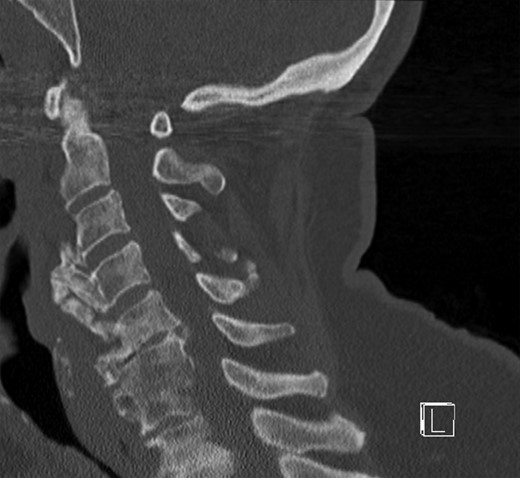

Surgical access to the cervical spine through a right-sided standard anterolateral approach showed osseous vegetations, which were strongly attached to the ventral spine and caused ventral displacement of the oesophagus. There was no infiltration of neighbouring tissues. Hyperostotic tissue at levels C3–C5 was carefully removed. Within 24 h, a single-dose 6-MeV photon of 7 Gy was applied. Indometacin treatment was initiated with 50 mg twice daily. A control CT examination showed successful removal of hyperostosis from segments C3 to C5 with intact vertebrae and proper configuration of the cervical lordosis without signs of instability (Fig. 4).

CT of the cervical spine in a sagittal view. Osteophytes from C3 to C5 are removed. Sagittal alignment of the spine is preserved.